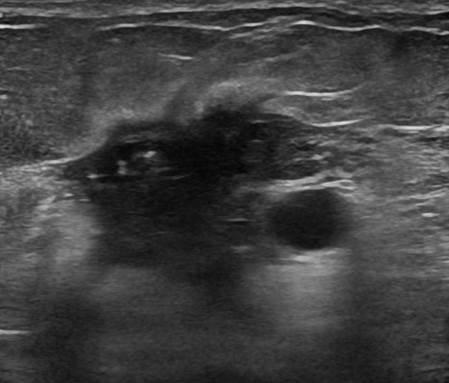

Ung thư vú

Ung thư vú - Ảnh 2

» Thông tin: Nữ giới – 58 tuổi.

» Lâm sàng: Khối tuyến vú.